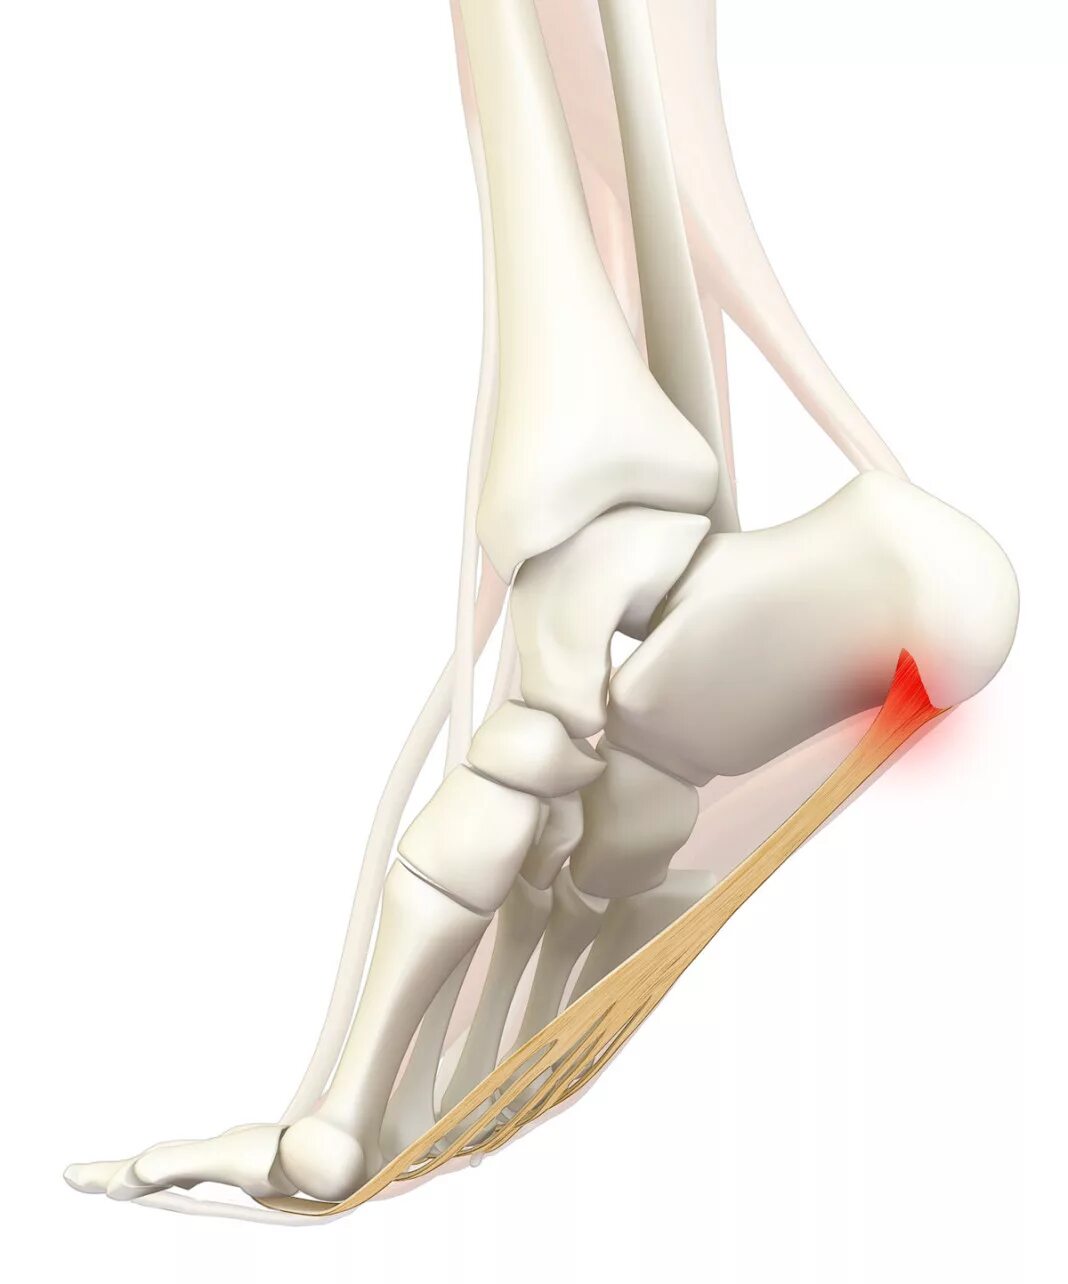

Как называется пяточная шпора